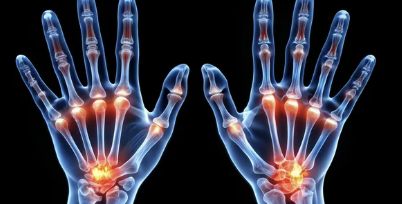

손가락 관절염은 손가락의 관절에 염증이 생기며 통증, 부종, 움직임 제한 등이 발생하는 질환으로, 주로 두 가지 유형으로 나뉩니다:

- 골관절염(퇴행성 관절염): 관절의 연골이 점차 닳아 없어지며 발생.

- 류마티스 관절염: 면역 체계 이상으로 관절에 염증이 생기고 손가락이 변형될 가능성이 높습니다.

1-2. 주요 특징

- 아침에 손가락이 뻣뻣하거나 움직이기 어렵다면 초기 증상일 수 있습니다.

- 심해지면 관절의 변형이나 움직임 제한이 생길 수 있습니다.